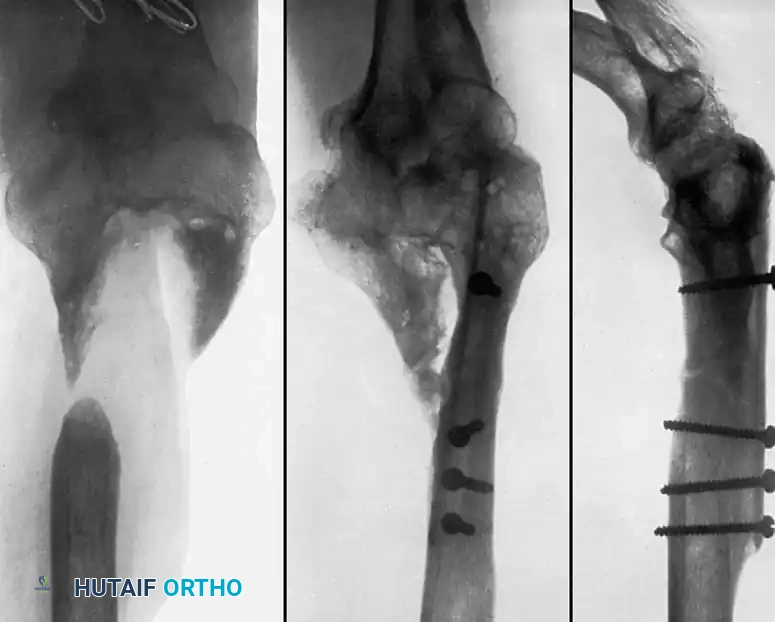

Medial Malleolus

A fracture of the medial malleolus occasionally fails to unite, especially after nonoperative (closed) treatment where periosteum or the deltoid ligament may interpose between the fracture fragments.

Surgery may be indicated for the few nonunions in which other serious complications of the fracture, such as advanced traumatic arthritis, are not seen on radiographs, and ideally if the injury is less than 2 years old. The standard surgical technique usually includes excision of the fibrous nonunion, application of autogenous bone grafts, and rigid internal fixation of the malleolar fragment.

When the nonunion is painful, it can be treated in one of three ways depending on the morphology of the fragment and the patient's functional demands:

- Bone Grafting and Fixation: When neither of the two previous treatments seems applicable (e.g., large fragment, young active patient, unstable mortise), formal bone grafting and internal fixation are indicated.

Technique 56-7: Sliding Graft for Medial Malleolus

- Exposure: Expose the nonunion through an anteromedial curved incision 10 cm long.

- Preparation: Reflect the periosteum anteriorly and posteriorly. Meticulously remove all interposed fibrous tissue from the nonunion site. Freshen the ends of the fragments using a curette or high-speed burr, but remove no bone from their deeper (articular) edges to avoid joint penetration. Carefully hollow out the distal fragment to receive the graft.

- Graft Harvest: Beginning at the nonunion and using an oscillating motor saw, harvest a cortical graft approximately 4 cm long and 1 cm wide from the proximal tibial fragment.

- Graft Placement: Displace (slide) the graft distally across the nonunion site and into the prepared trough in the distal fragment.

- Fixation: Hold the distal fragment in its precise anatomic position, restoring the mortise. Transfix the fragments and the sliding graft with a fully threaded or partially threaded 4.0 mm cancellous lag screw.

- Augmentation: Place cancellous bone chips (harvested from the proximal metaphysis) around the graft site to enhance osteoconduction.

- Closure: Confirm the position of the graft, the screw, and the joint space with intraoperative fluoroscopy. Close the wound in layers.

Fig. 56-18 Nonunion of medial malleolus treated by sliding graft.

Postoperative Protocol: A non-weight-bearing cast is applied from the toes to just distal to the knee. At 2 weeks, sutures are removed, and a walking cast or rigid boot is applied. Partial weight-bearing is allowed during the next 2 weeks, advancing to full weight-bearing thereafter. The immobilization is discarded when radiographs confirm osseous union, typically at 8 to 10 weeks.